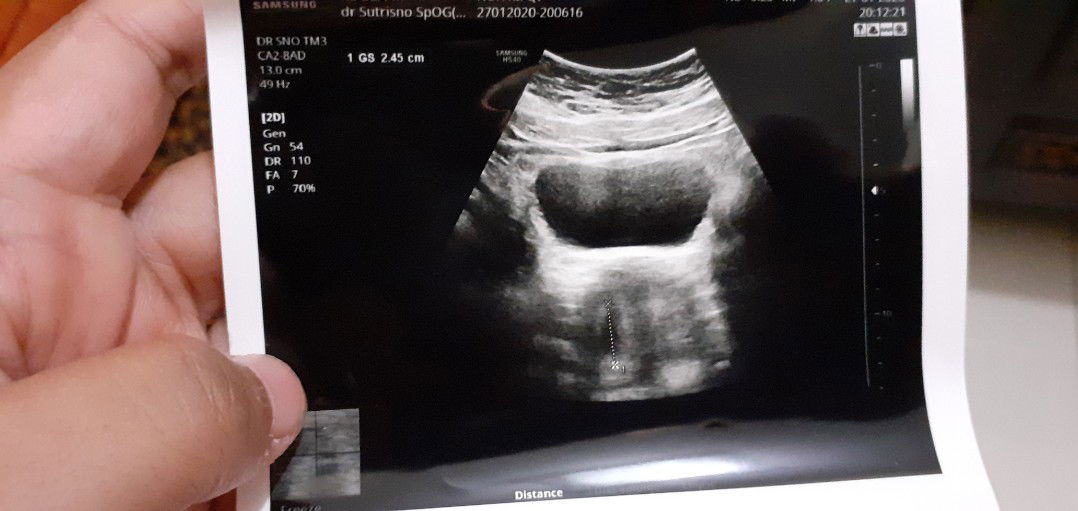

kantung kehamilan lonjong

Bund aku kmrn dh kontrol nih usia 1½bulan khamilan..nah kantong aku bntuknya kyk gt... biasanya kn bulet gt to .. dokter bilang normal² aja cma g puas gt g bsa nnya².. orgnya buru² soalnya antrian bejibun.. Ad g bunda² dsini 6 minggu kantung kehamilan lonjong gt.. sehat² aja babynya smpe gede smpe lairan?? Kta tmnku yg bidan g bulet bukan brti abnormal.. cma aku worry aja.. Gmn bund???

Barusan k dokter nih bund rekomen temen katanya dokternya enak.. coba deh k sana.. emg sih utk usg hasilnya lbh jelas.. 2 hr yg lalu udh tlp dulu nih.. dpt lah no.9.. nah pas dtg ni tadi subhanallah antrinya.. bikin punggungku capek bangt pngen rebahan.. Trs udh 1 jam an lbh nggu.. pas masuk g d tnyain apa2... lgsg usg.. g d jlsin apanya gmn balik kapan .. cma blg tes positif ya.. y mmg hamil.. 1 ½ bulan.. gt doank.. klo aku g blg pernah flek sminggu lalu y g d ksi penguat... suami yg plg kerja capek.. krg tdr.. udh cemberut aja.. dh gt.. obtnya lbh mahal dr dokter pertama aku.. pas tgl tua lagi.. suami syok.. n g nyaman bgt.. pd akhirnya dia memutuskan ntr bln dpn balik lgi k dokter lama aja.. Tp alhamdulillah dokter blgnya sih ni td g butuh pnguat krn ad riwayat flek d kasi lah.. dh gt doank.. y ampun klo kta org jawa g sumbut sma antrinya.. dokternya kurang komunikatif.. mgkin krn pasien yg buanyak bgt... ? tp gpp lah penting sehat smuanya.. btw msih belm kliatan sih babynya.. next balik 4 minggu lagi aja.. Btw.. bunda yg ad riwayat flek.. tp dh berhenti..gmn pengalamannya andai g minum obt penguat gpp ta? Td soalnya nebus obat cma 10 aja.. g d tebus smua.. makasih y bund

Dr awal kehamilan sering flek bund.. td malam lumayan.. dan brusan cek dokter katanya kantung kehamilannya ad tp bentuknya kurang bagus.. usia 5 minggu..2 minggu lagi d suruh balik.. tp selama it harus observasi gmn perkembangan fleknya.. jika banyak dan sering sgra k RS.. jika sdikit² tdk apa².. tp sma dokter d suruh minum vit terus dan d kasi obat penguat.. pregnolin.. Doakan baik² saja y bund dan ad perkembangan 2 minggu lagi...